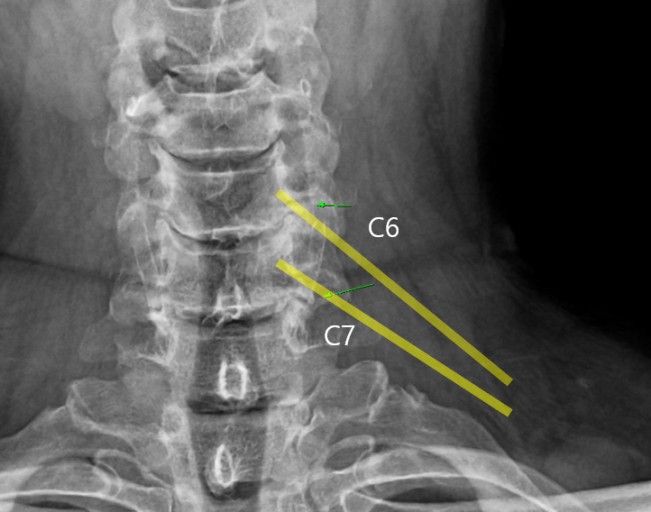

오늘은 목 건강을 위협하는 질환, **목디스크(경추 추간판 탈출증)**의 증상에 대해 이야기하려 합니다. 목디스크는 목뼈 사이에 있는 디스크가 제자리를 벗어나 신경을 압박하면서 발생하는 질환입니다.

목디스크는 목 통증뿐만 아니라, 신경 압박으로 인해 신체의 다른 부위에도 다양한 증상을 유발합니다. 다음은 목디스크 환자들이 흔히 겪는 10가지 주요 증상입니다.

- 설명: 목에서 팔로 내려가는 신경이 디스크에 의해 눌리면서 팔, 손, 손가락이 저리고 찌릿한 통증이 나타납니다. 저림 증상은 특정 손가락에서만 나타나기도 하고, 양쪽 팔 모두에서 나타나기도 합니다.